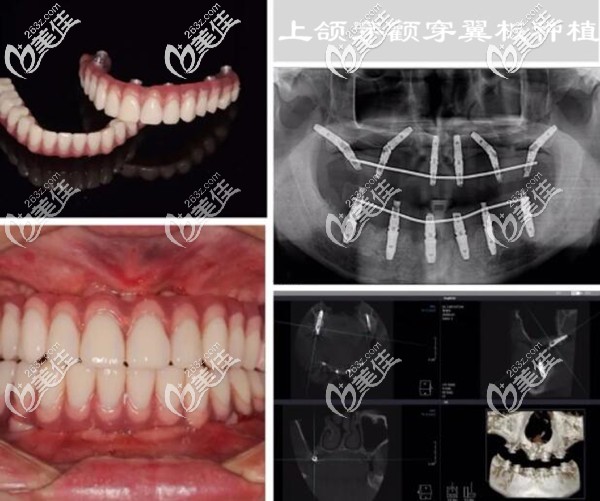

我今年50岁,是做穿颧穿翼板种植牙的受益者;从戴单颗的烤瓷牙到全口的活动假牙,已有10多年了;现在的牙槽骨萎缩、条件极差,假牙动不动就掉了,常年吃不好饭,肠胃也跟着受累。

因为,牙槽骨量太少,做传统的种植牙要大量植骨,而且还要等3个月左右才能种牙。后来,上颌做的是双侧穿翼板种植,不用植骨;整个手术过程用了2个小时左右(不过手术前挺麻烦的,做了好多检查)。

其实,我在做手术前也很紧张、很担心,怕手术会有风险,担心留下啥后遗症;不过看了术后多次复查的CT片,我终于放心了。

下面是我做穿颧穿翼板种植牙后的照片和CT片▼